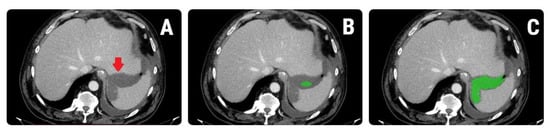

2.5. Texture Analysis

2.5.1. Image Pre-Processing and Segmentation